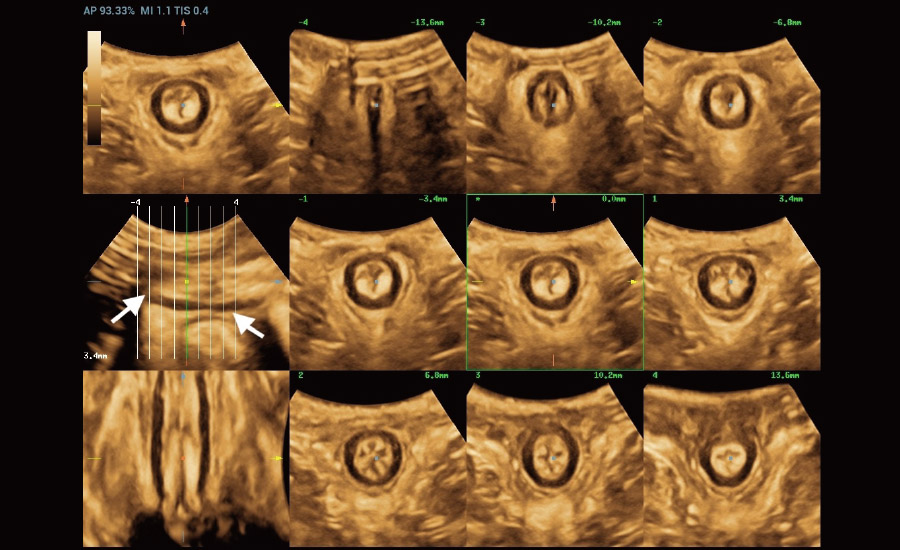

Combining advanced algorithms and domain-specific knowledge, the innovative Smart Scene solution enables auto identification of tissue characteristics and provides organ-specific diagnosis with full-stack intelligence. Based on auto scenario identification, the solution not only realizes smart 2D scanning with auto settings and measurements, but also delivers 3D full-stack intelligence in every step from volume imaging optimization to the difficult 2D plane acquisition, and quantification throughout whole procedure. It helps a lot in reducing the dependency on clinical skills, while increasing diagnostic accuracy, confidence and efficiency.

Fertility

Obstetrics